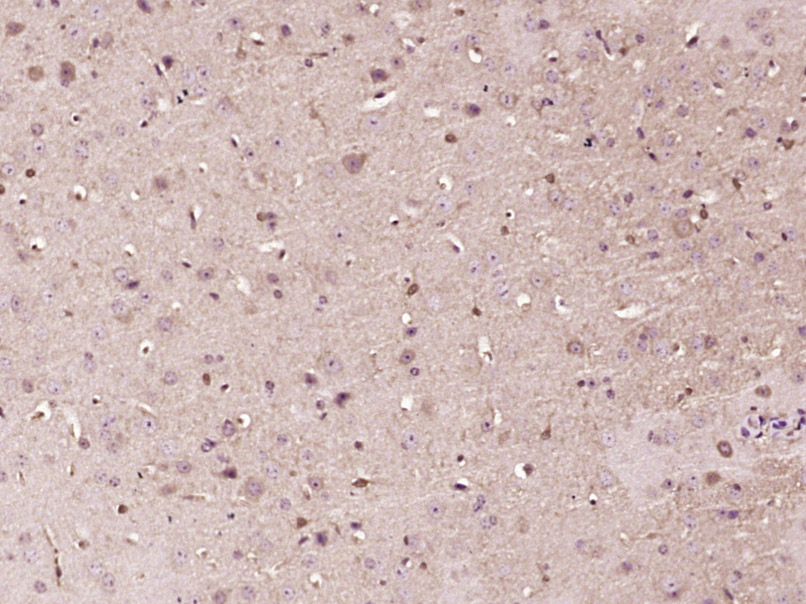

Paraformaldehyde-fixed, paraffin embedded (Mouse brain); Antigen retrieval by boiling in sodium citrate buffer (pH6.0) for 15min; Block endogenous peroxidase by 3% hydrogen peroxide for 20 minutes; Blocking buffer (normal goat serum) at 37°C for 30min; Antibody incubation with (P2X2) Polyclonal Antibody, Unconjugated (bs-23813R) at 1:400 overnight at 4°C, followed by operating according to SP Kit(Rabbit) (sp-0023) instructionsand DAB staining.